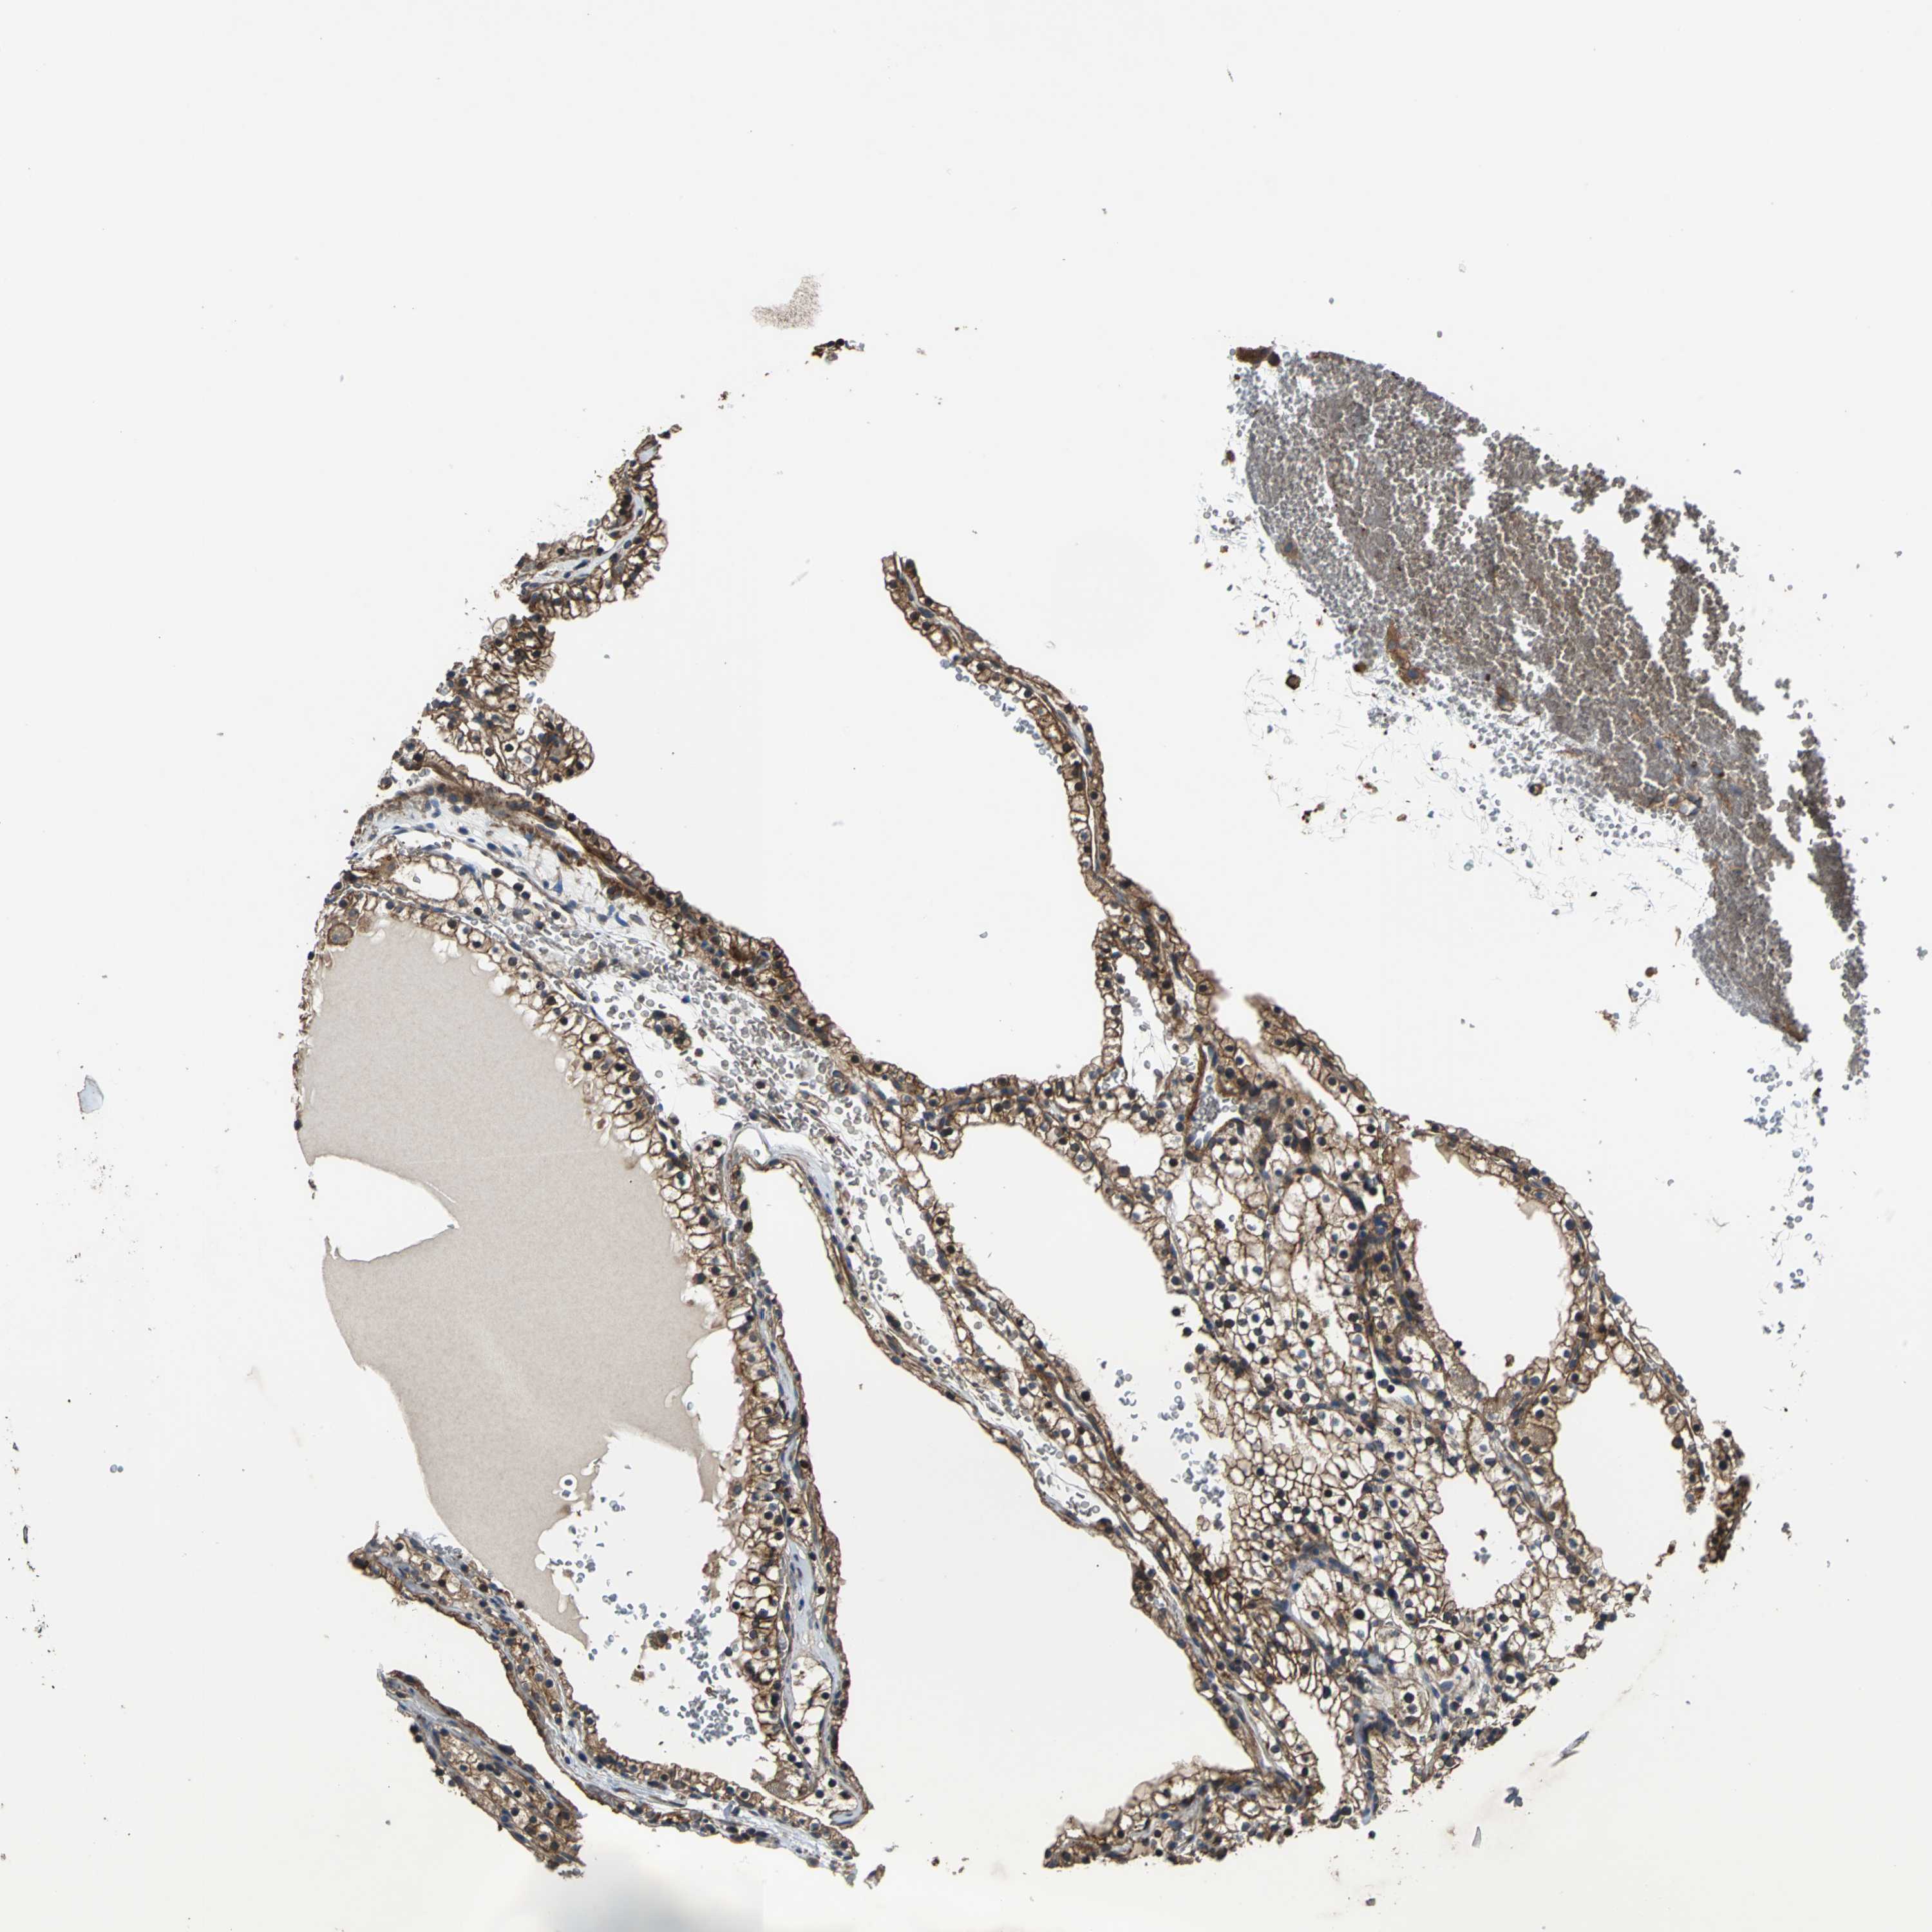

KIDNEY RENAL PAPILLARY CELL CARCINOMA (TCGA) - Interactive survival scatter ploti

The Survival Scatter plot shows the clinical status (i.e. dead or alive) for all individuals in the patient cohort, based on the same data that underlies the corresponding Kaplan-Meier plots. Patients that are alive at last time for follow-up are shown in blue and patients who have died during the study are shown in red.

The x-axis shows the expression levels (FPKM) of the investigated gene in the tumor tissue at the time of diagnosis. The y-axis shows the follow-up time after diagnosis (years). Both axes are complimented with kernel density curves demonstrating the data density over the axes. The top density plot shows the expression levels (FPKM) distribution among dead (red) and alive patients (blue). The right density plot shows the data density of the survived years of dead patients with high and low expression levels respectively, stratified using the cutoff indicated by the vertical dashed line through the Survival Scatter plot. This cutoff is automatically defined based on the FPKM cutoff that minimizes the p-score. The cutoff can be changed by dragging the vertical line or by entering a cutoff value in the square labeled "Current cut-off".

Under the Survival Scatter plot the p-score landscape (black curve; left axis) is shown together with dead median separation (red curve; right axis). Dead median separation is the difference in median mRNA expression between patients who have died with high and low expression, respectively. It is calculated as follows: median FPKM expression of dead patients with high expression - median FPKM expression of dead patients with low expression. This is intended to aid the user in visually exploring custom cutoffs and the associated p-scores and dead median separation.

Individual patient data is displayed and can be filtered by clicking on one or more of the category buttons on the top of the page. Categories describing expression level and patient information include: high, low, alive, dead, female, male and tumor stages. The scale of the x-axis can be toggled between linear and log-scale by clicking on the "x log" button. Mouse-over function shows TCGA ID, patient information and mRNA expression (FPKM) for each patient.

& Survival analysisi

Kaplan-Meier plots summarize results from analysis of correlation between mRNA expression level and patient survival. Patients were divided based on level of expression into one of the two groups "low" (under cut off) or "high" (over cut off). X-axis shows time for survival (years) and y-axis shows the probability of survival, where 1.0 corresponds to 100 percent.

PARVA is not prognostic in Kidney Renal Papillary Cell Carcinoma (TCGA)

Best expression cut offi

Based on the FPKM value of each gene, patients were classified into two groups and association between prognosis (survival) and gene expression (FPKM) was examined. The best expression cut-off refers the FPKM value that yields maximal difference with regard to survival between the two groups at the lowest log-rank P-value. Best expression cut-off was selected based on survival analysis .

When clicking on this number, the vertical dashed line indicating cut-off, the interactive survival plot, and the Kaplan-Meier curve will be adjusted to show results based on the best expression cut-off.

: 10.56